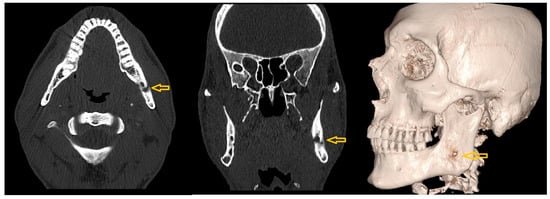

- Case 2

| 2 | Female | 10 | Bilateral hyperplasia of the coronoid processes |

OPG CT | 17 mm | Bilateral coronoidectomy | 45 mm |